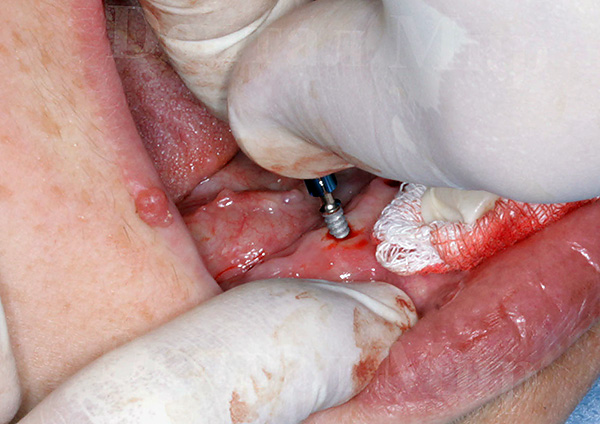

Quanto ao implante transgengival - se você ler os materiais publicitários, ele será realizado através da chamada "punção" das gengivas. De fato, a incisão mais verdadeira é feita na forma de um círculo com a ajuda de um mucótomo circular. Ou seja, embora o anúncio afirme que o implante não é cirúrgico e que, segundo eles, é realizado sem incisão, mas apenas por meio de uma "punção", no entanto, estritamente falando, há uma pequena operação com uma incisão circular nas gengivas.

Como observado acima, o implante transgengival de dentes é hoje posicionado por algumas clínicas como a tecnologia de instalação de implantes dentários sem cortar as gengivas, ou seja, através de uma punção na mucosa. O que é essa "punção", já descobrimos - na realidade, na realidade, uma punção é chamada de incisão circular da gengiva usando um mucótomo.

Em contraste com a técnica clássica, durante o implante transgengival, as lesões dos tecidos moles são menos significativas - a incisão parece muito clara, quase o diâmetro da gengiva anterior instalada no pilar do implante. Ou seja, um "implante sem cirurgia" é, obviamente, um mito e uma manobra publicitária, mas com um mínimo de trauma no tecido gengival, a implantação é bem possível.

O fato de a gengiva durante o implante “não cirúrgico” sofrer lesões mínimas não exclui a necessidade de perfurar o osso da mandíbula usando um conjunto consistente de fresas. Afinal, a perna do implante é uma espécie de parafuso de titânio que você precisa literalmente parafusar no orifício.

Consequentemente, após realizar uma incisão circular com um mucótomo e remover o círculo gengival excisado, segue-se um estágio completamente padrão de preparação do orifício para a colocação do implante - expansão e aprofundamento dos cortadores.

Se a instalação do implante for realizada sem gabaritos cirúrgicos especiais, ela consistirá nas seguintes etapas principais, realizadas no mesmo dia:

- Um corte circular é realizado ("punção");

- O furo se expande para o diâmetro desejado e se aprofunda;

- Em seguida, segue a instalação do implante e controla a profundidade de sua introdução;

- Depois disso, o gingiva anterior é instalado;

- Em conclusão, o paciente cumpre as recomendações prescritas pelo médico (antibioticoterapia, regime de economia, etc.).